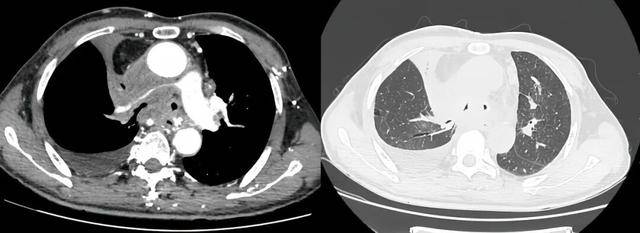

同期置入支架后狭窄明显改善

介入手术室里,一场无声的战役打响。麻醉科主任闫华凭借高超技术,成功为患者通气建立安全通路,为手术的实施奠定基石。介入科主任贺光辉带领团队细致操作,将一枚Y形气管支架在X线引导下输送至预定位置后精准释放,原本被肿瘤挤压得只剩一丝缝隙的气道被稳稳地撑开。紧接着一枚肺动脉覆膜支架置入到受压变窄的右肺动脉主干内并准确释放,再次造影,使得右肺动脉血流迅速得到改善。